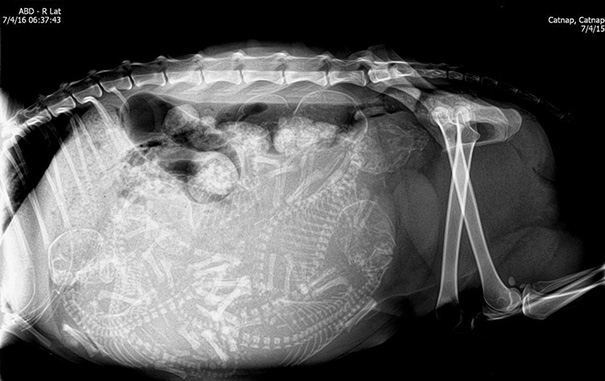

Unikāli rentgena attēli ar dzīvniekiem gaidībās

Bieži negadās publiski redzēt dzīvnieku rentgena uzņēmumus. Turklāt šie rentgena uzņēmumi ir veikti dzīvniekiem, kuri ir mazuļu gaidībās. Tagad ikvienam ir iespēja ielūkoties, kā dzīvnieku mazuļi attīstās savu mammu vēderos.